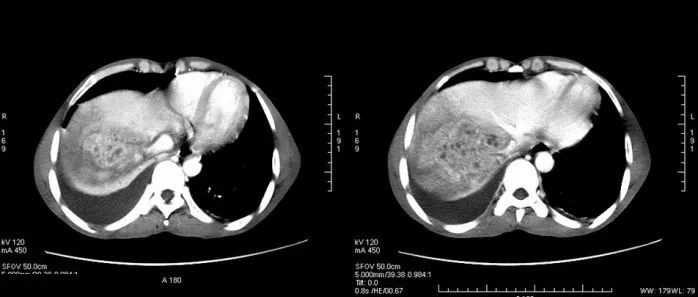

肝脓肿!

医学影像  yxyx-app  医学影像APP,打造伴随医生快速成长的影像学习社区。与影像园(Xctmr.com)一起提供最全面的影像案例库、基础(解剖、病理、影像诊断)知识、影像技术及考题等,为医生提供最佳的医学影像参考。【所属科室】消化科【基本资料】患者,男,36岁【主诉】上腹部胀痛3周余伴发热【体格检查】上腹部压痛(+),无明显反跳痛,肝区叩痛(+),腹肌稍紧,未扪及明显包块,移动性浊音(-)...